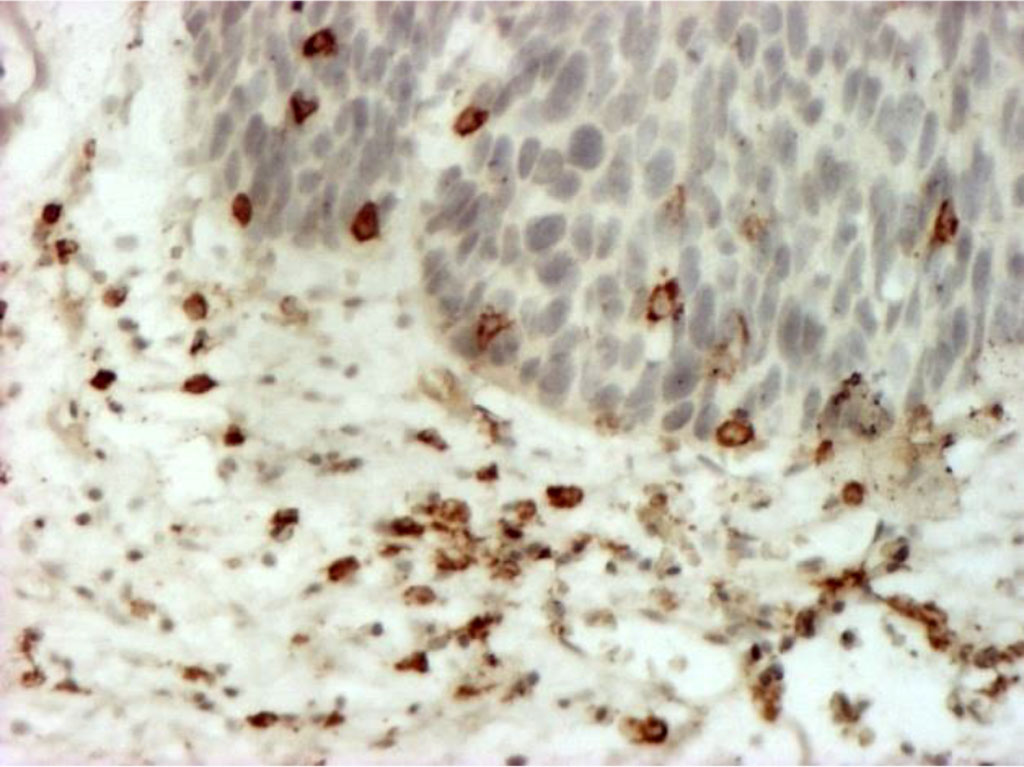

Immunohistochemical typing of cellular stromal infiltrates revealed a predominance of CD4+ T-lymphocytes, distributed evenly, in places forming small clusters (Fig. 4).

Fig. 4. Stromal lymphocytes (T-helpers) (CD4+), forming small clusters in places. Immunohistochemical staining with MAb to CD4+ X400.

No significant correlation was found between the quantitative and qualitative composition of cellular infiltrates and such factors as the patient's age and the degree of VIN differentiation. For differentiated VIN, the average number of immunocompetent cells per 1 mm² was 13.3±1.6 in the stroma, and 4.7±1.3 within the field of view. Lymphocytes predominated in the infiltrates (87.6±4.9%, p<0.001). Undifferentiated forms of VIN associated with vulvar carcinoma have a low density of immune cellular and inflammatory infiltrates. The quantitative and qualitative composition of cellular infiltrates in VIN1, VIN2 and VIN3 do not have significant intergroup differences (p> 0.05), but can be used to assess the degree of VIN differentiation and differential diagnosis of VIN3 and invasive carcinoma. The results are presented in Table 2.